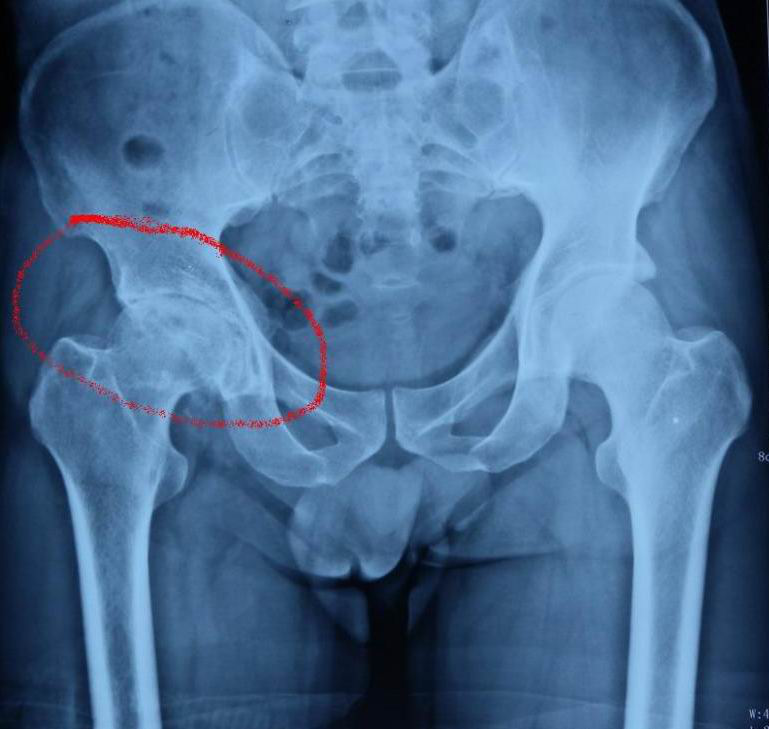

術(shù)前拍攝髖關(guān)節(jié)X線片可診斷,必要時(shí)檢查髖關(guān)節(jié)CT。

術(shù)前X線片